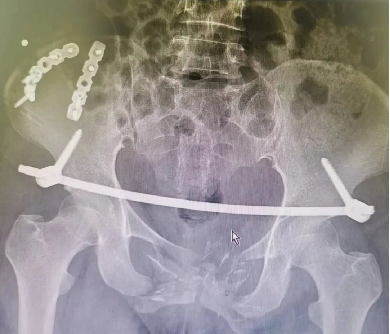

患者黄某,因车祸外伤导致全身多处疼痛入院,入院即因失血性休克于ICU监护,完善检查显示双侧耻骨粉碎性骨折、右侧髂骨多处骨折、右骶髂关节脱位,提示骨盆前-后环均不稳定。

对于此种前后环均严重失稳的复杂骨盆骨折的治疗,保守治疗不仅需长期卧床,易导致褥疮、肺部感染、泌尿系感染及深静脉血栓风险,同时势必影响后期功能恢复,严重降低患者未来生活质量。传统开放术式手术切口大、手术时间长,手术难度极大,同时存在盆腔内血管神经及膀胱的医源性损伤风险,以往,遇到此种严重病情只能依赖上级医院专家来院手术指导,但基于近期成功开展的骨盆微创治疗的经验支持,外一科董明主任反复研究患者病情及影像,充分考虑手术创伤与风险后,决定开展骨盆骨折有限切开复位内固定术。

经充分术前准备,由董明主任、余策略主治医师、叶强医师为患者在全麻下仅用不到2小时便成功完成了手术,术中出血量少,术后第二天患者就可以床上坐起及翻身,功能恢复良好。